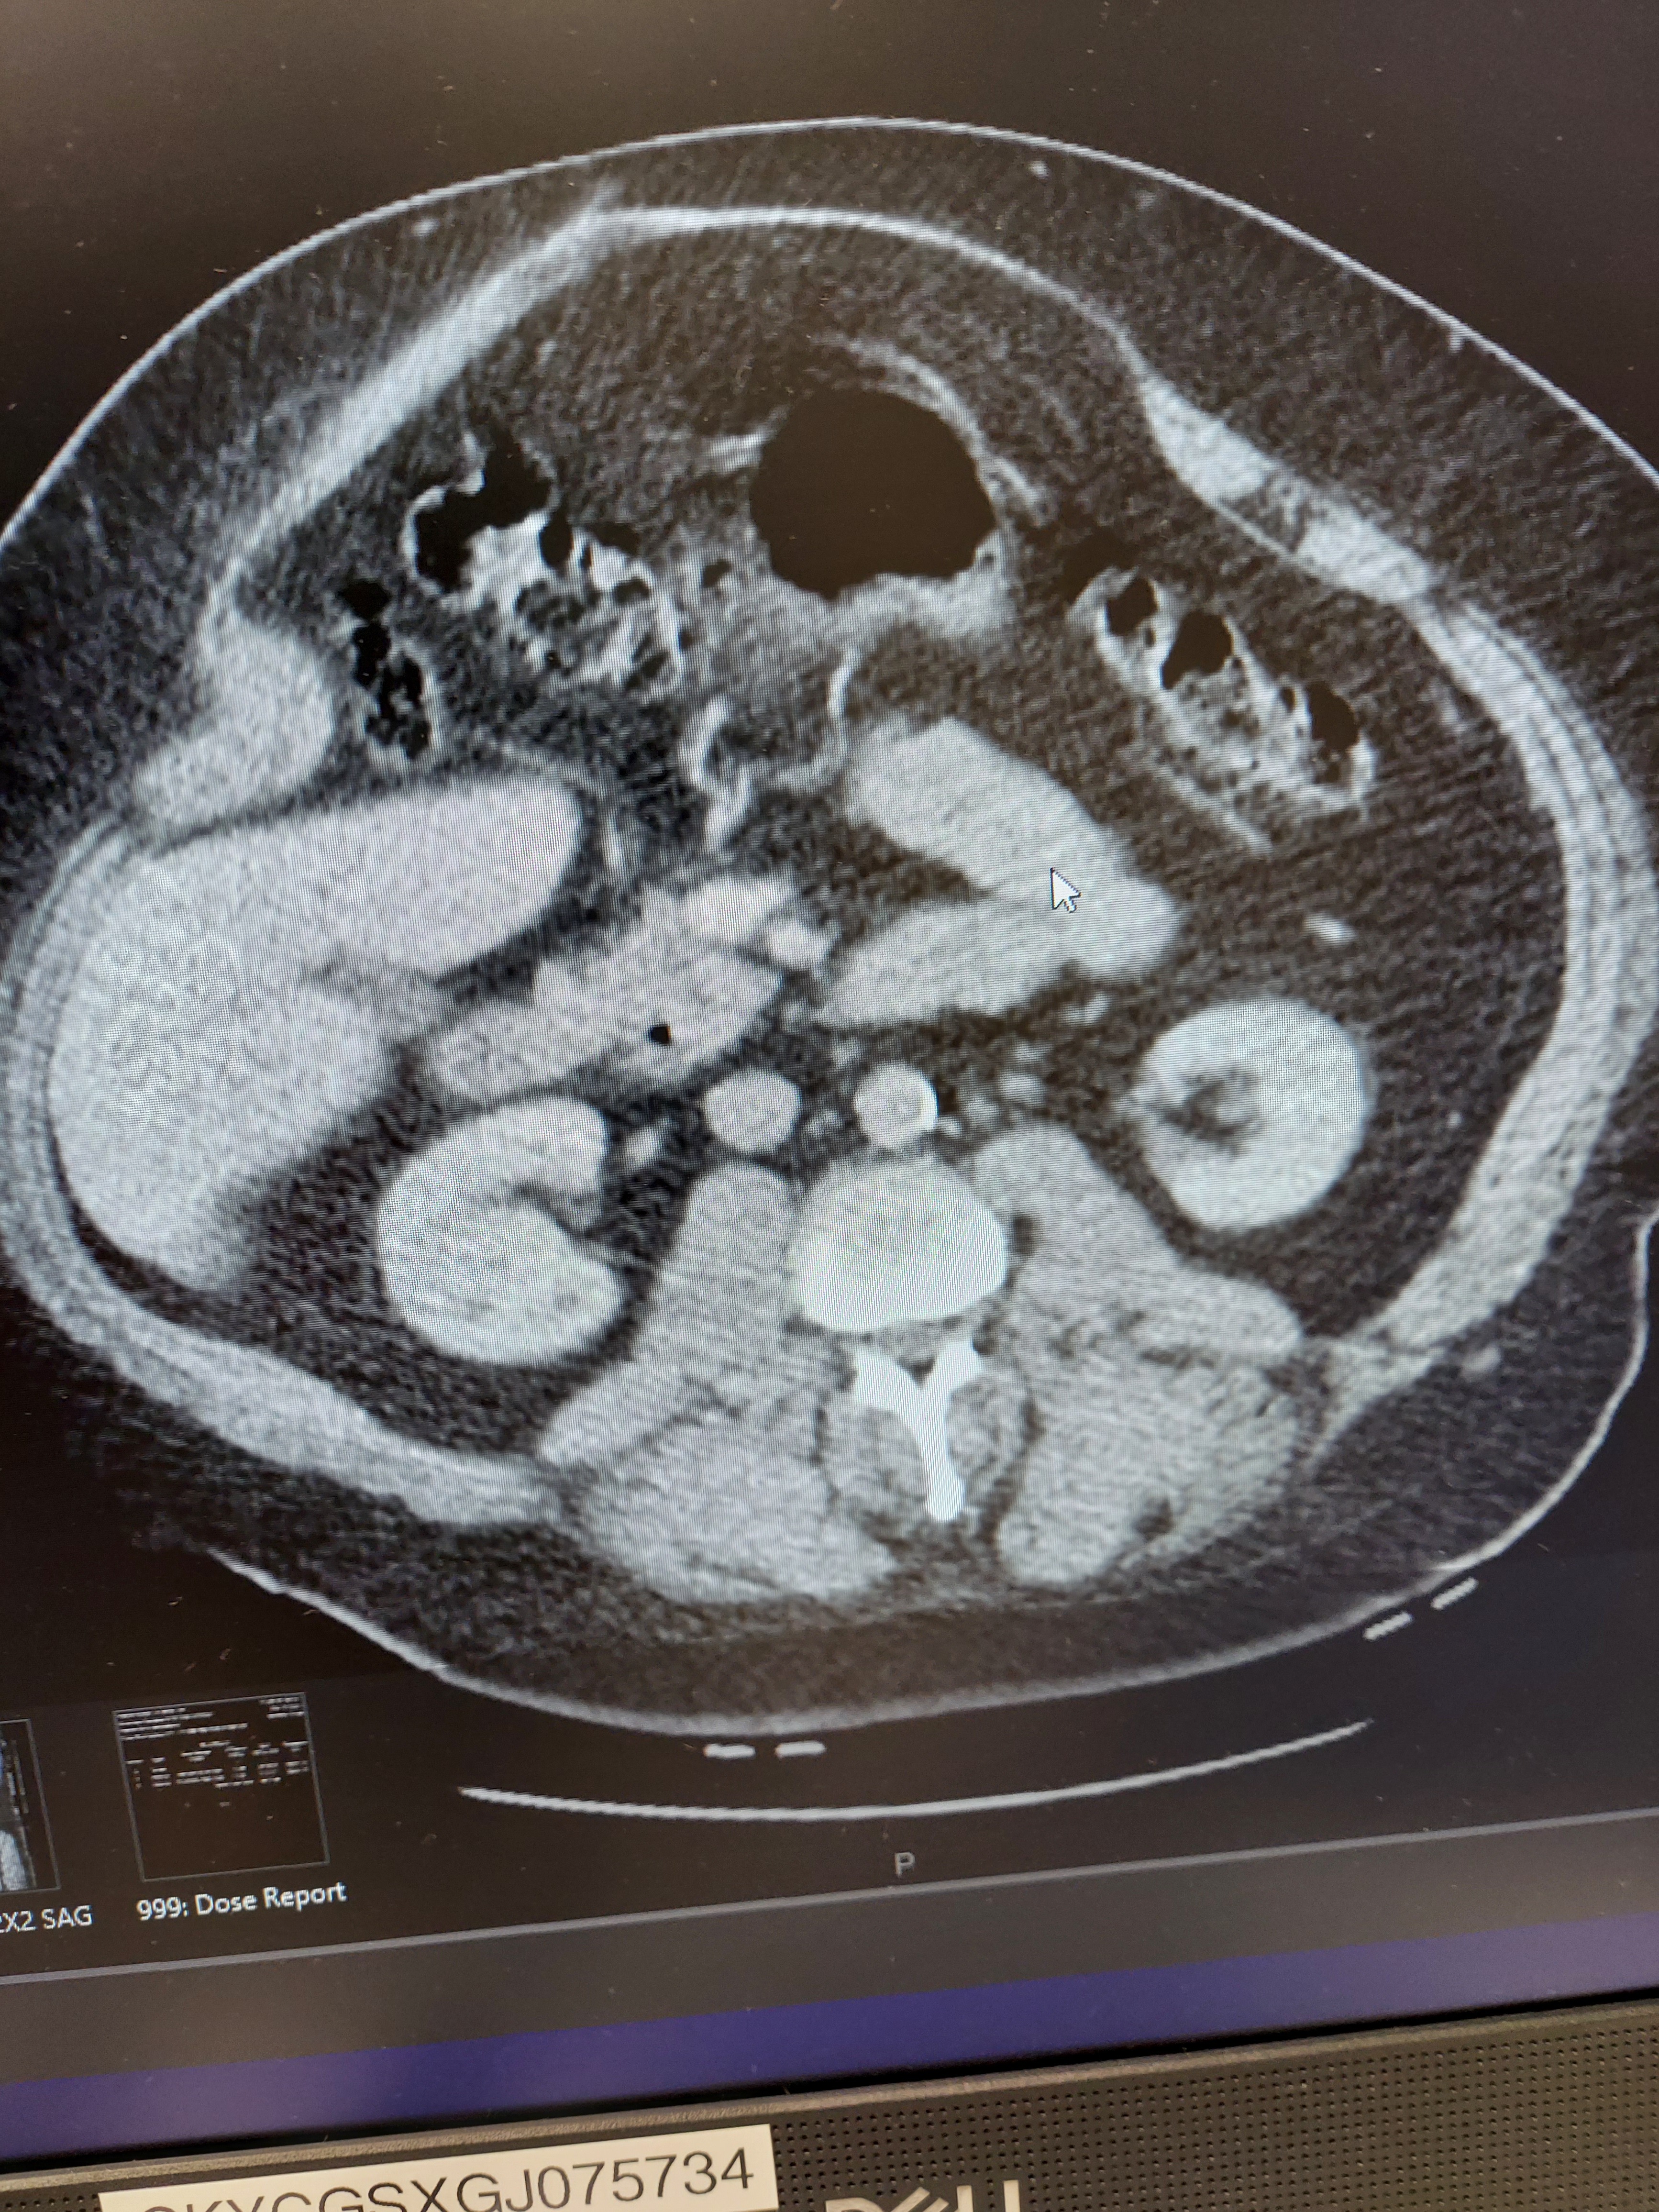

My name is Luc, and for the past eight years, I've been living with a surgical hernia. Because it's gone untreated for so long, I'm now facing additional health complications that make daily life even more challenging. On top of my health struggles, I recently went to eviction court and learned that I'll need to find a new place to live soon. It's been overwhelming trying to manage my health while also worrying about where I'll be able to call home next.